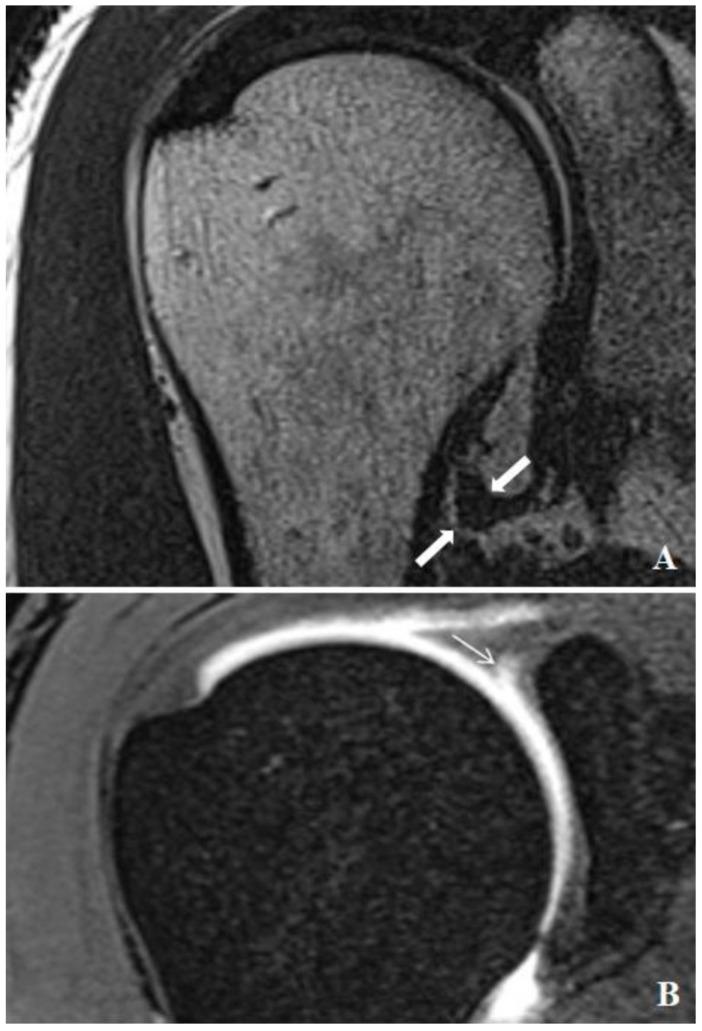

This study aimed to evaluate the relationship between SLAP lesions and the shoulder joint capsule thickness via MR arthrography. Understanding the relationship between SLAP lesions and the joint capsule thickness is important because an increased capsule thickness may indicate chronic inflammation and contribute to persistent pain and dysfunction. These findings have significant clinical implications for the diagnosis, management, and treatment strategies of shoulder joint pathologies. We retrospectively analyzed the MR arthrography results of 78 patients who underwent shoulder imaging at Düzce University Medical Faculty between October 2021 and November 2024. The study included patients diagnosed with SLAP lesions and compared them with a control group without such pathology. Data on joint capsule thickness at the level of the axillary recess, SLAP lesion type, cuff pathology, and demographic information were collected and analyzed. The study included 32 patients with SLAP lesions and 46 control subjects. The mean age of the patients was 44.75 ± 14.18 years, whereas the control group had a mean age of 38.76 ± 13 years. The patient group presented a significantly greater mean anterior capsule thickness (3.13 ± 1.28 mm vs. 1.72 ± 0.7 mm, = 0.0001), posterior capsule thickness (3.35 ± 1.32 mm vs. 1.95 ± 1.06 mm, = 0.0001), and maximum capsule thickness (3.6 ± 1.32 mm vs. 2.06 ± 1.01 mm, = 0.0001) in the axillary recess. SLAP type 2 lesions were the most common type (43.76%) in the patient group. This study revealed a significant association between SLAP lesions and an increased shoulder joint capsule thickness. These findings suggest that MR arthrography is an effective tool for assessing the joint capsule changes associated with labral tears, contributing to the better diagnosis and management of shoulder joint pathologies in clinical practice.

该研究包括 32 名 SLAP 病变患者和 46 名对照组。患者组的平均年龄为 44.75 ± 14.18 岁,而对照组的平均年龄为 38.76 ± 13 岁。患者组的前囊厚度(3.13 ± 1.28 毫米)、后囊厚度(3.35 ± 1.32 毫米)和最大囊厚度(3.6 ± 1.32 毫米)明显大于对照组(1.72 ± 0.7 毫米, = 0.0001)、(1.95 ± 1.06 毫米, = 0.0001)和(2.06 ± 1.01 毫米, = 0.0001)。在腋窝中。患者组中最常见的 SLAP 病变类型是 2 型(43.76%)。